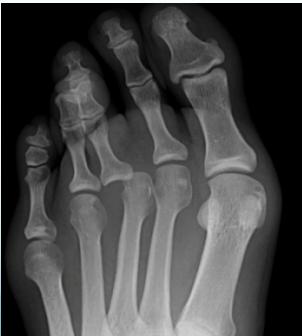

| Silicone Spacer/Splint | Lower Limb | Adolescent hallux valgus (cosmetic complaint); initial treatment choice in mild cases | N/A | , ![]() |